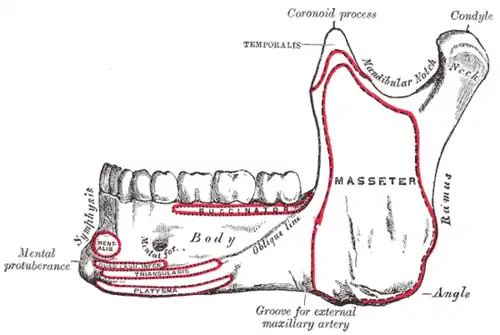

Outer surface of mandible. Mentalis is indicated by the red circle at left.

Outer surface of mandible. Mentalis is indicated by the red circle at left. Position of mentalis (red)